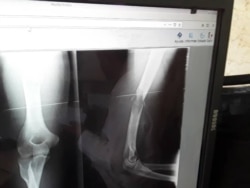

"El día 31 de octubre, la silla de ruedas que él utiliza se la dieron a otro preso", lo que obligó a Pérez Carmenate a permanecer en cama. Además de esto, el brazo operado el 17 de octubre no recibió curas, ni le fue cambiada la venda pese a la suciedad", detalló la madre del reo.

Pérez Carmenate permaneció 40 días sin asistencia médica en prisión hasta que fue operado de la lesión en un brazo, el 8 de octubre, en el hospital Clínico Quirúrgico de Las Tunas, y luego regresado a prisión.